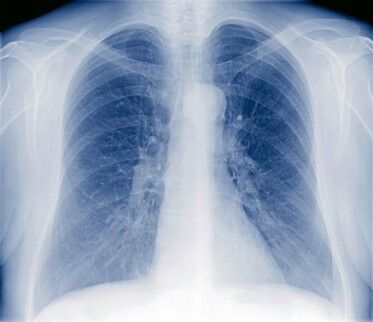

Pneumonia in Preemie Babies: A Complication of Poor Lung Function

Preemies who experience respiratory problems as a complication of early birth are at greater risk of developing lung infections such a pneumonia. In preemie babies not only does the infection from the pneumonia bug cause problems, but the inflammation caused by the infection can also reduce the airspace where the oxygen and carbon dioxide exchange takes place. Fortunately, the condition is one which is not uncommon, therefore easily detected and treated. The primary treatment for pneumonia in preemie babies is supplementary oxygen and equally importantly antibiotics to kill off the infection.